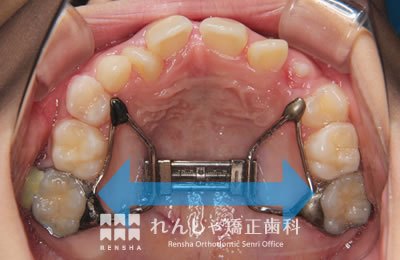

中高生

永久歯列はほぼ完成してしますが、歯列を側方だけでなく後方へも拡大し、埋まっていた右上奥歯を引っ張り出しています。

| 主訴 | 埋まったままでてこない歯がある |

|---|---|

| 診断名 | Angle Class II 小臼歯の埋伏と叢生を伴う上顎前突 |

| 初診時年齢 | 13歳5か月 |

| 装置名 | マルチブラケット装置 |

| 抜歯非抜歯 | 非抜歯 |

| 治療期間 | 2年3か月 |

| 費用の目安 | 約82万円+消費税(検査料金、都度の処置費用等も合わせた総額) |

| リスク副作用 | 歯の移動に伴う軽微な歯根吸収、歯槽骨吸収、歯肉退縮(本症例では軽度の歯根吸収を認めた)、矯正器具装着中のカリエスリスク増大(本症例ではカリエス発生無し) |